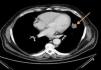

Thoracoabdominal tomography revealed a left paracardiac nodular image with 4cm×2cm diameter, with irregular limits, aspects of a probable connection to a neoplastic lesion (Fig. 2).